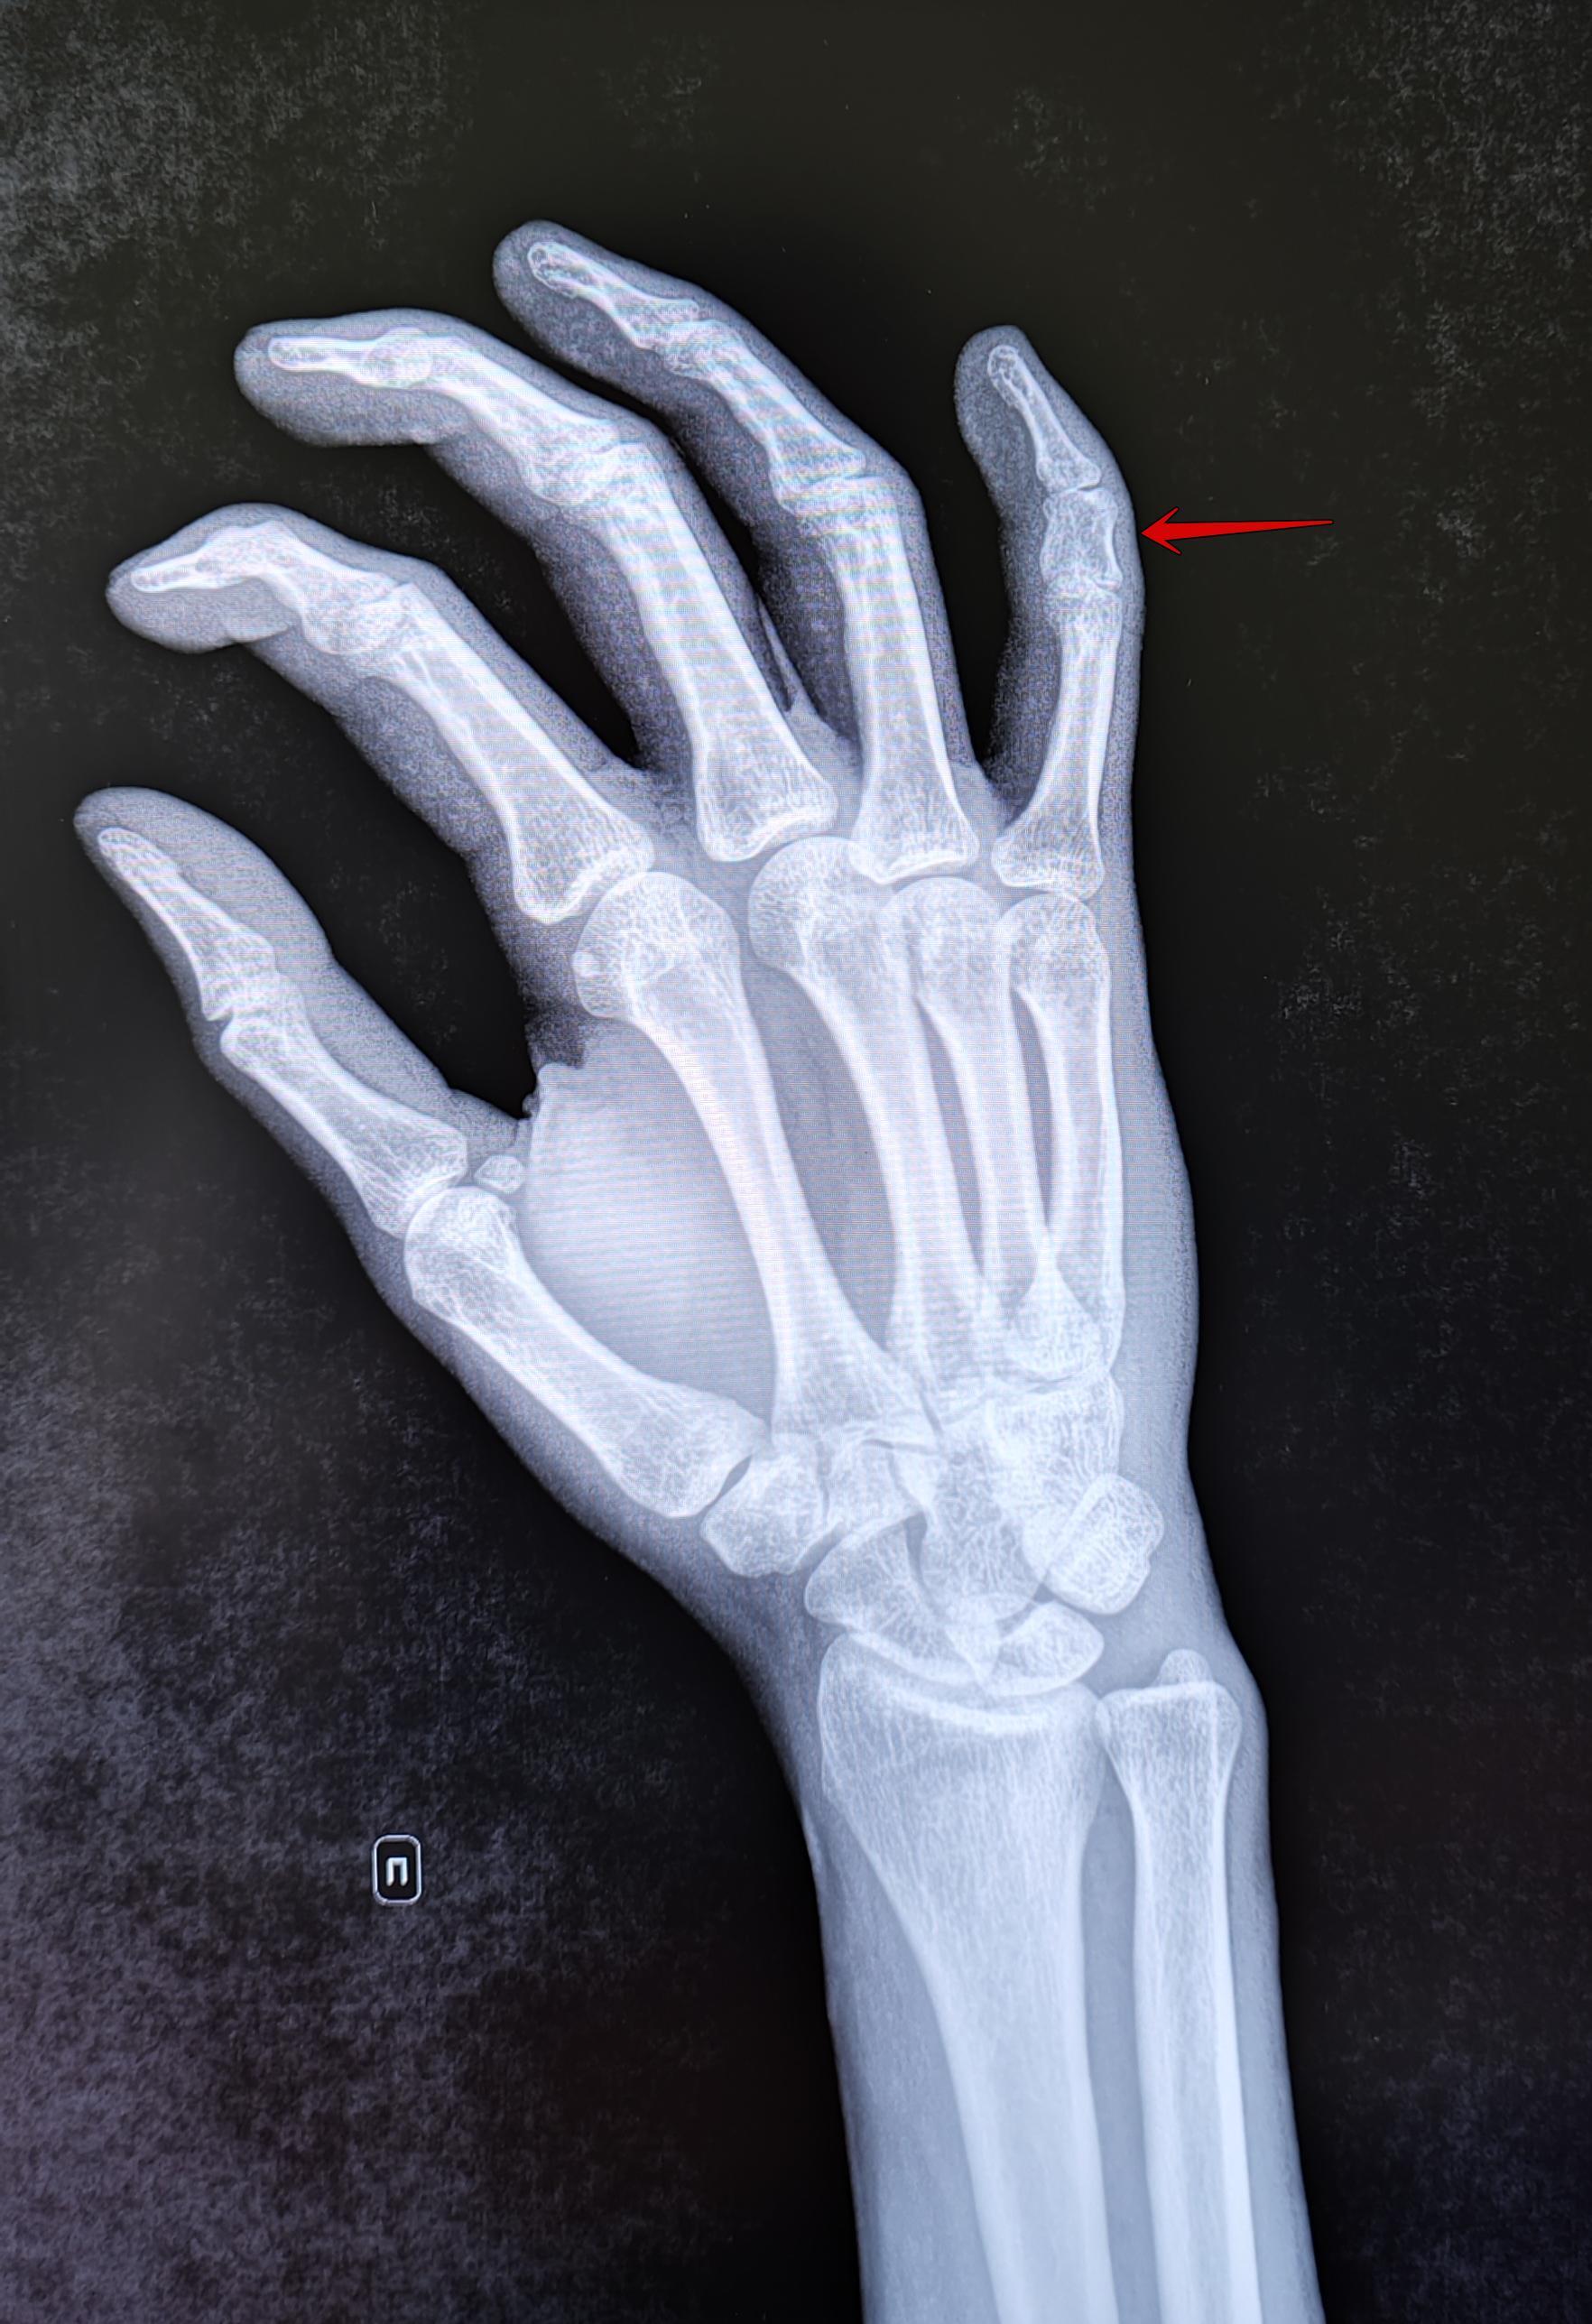

На Р-граммах правой кисти в 2х проекциях: травматических, деструктивных изменений не выявлено. Структура костной ткани не изменена. Средняя фаланга пятого пальца укорочена, утолщена. По остальным отделам кисти-без явной костной патологии.

Заключение: Врожденная аномалия развития правой кисти- брахидактилия (брахифалангия) средней фаланги пятого пальца правой кисти.